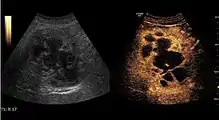

Hepatic hemangioma (2D). The lesion is located in the left hepatic lobe. Note precise delineation, their increased echogenity and the heterogeneous internal structure.

Hepatic hemangioma (CEUS). Progression of CA from the periphery toward the center of the lesion is evidenced by examination at various time intervals (a – arterial phase; b – late phase).

It is the most common liver tumor with a prevalence of 0.4 – 7.4%. It is generally asymptomatic but also can be associated with pain complaints or cytopenia and/or anemia when it is very bulky. It is unique or paucilocular. It can be associated with other types of benign liver tumors. Characteristic 2D ultrasound appearance is that of a very well defined lesion, with sizes of 2–3 cm or less, showing increased echogenity and, when located in contact with the diaphragm, a "mirror image" phenomenon can be seen. When palpating the liver with the transducer the hemangioma is compressible sending reverberations backwards. Doppler exploration reveals no circulatory signal due to very slow flow speed. CEUS investigation has real diagnosis value due to the typical behavior of progressive CA enhancement of the tumor from the periphery towards the center. The enhancement is slow, during several minutes, depending on the size of hemangioma and on the presence (or absence) of internal thrombosis. During late (sinusoidal) phase, if totally "filled" with CA, hemangioma appears isoechoic to the liver. Deviations from the above described behavior can occur in arterialized hemangiomas or those containing arterio-venous shunts. In these cases, differentiation from a malignant tumor is difficult and requires other imaging procedures, follow up and measurements of the tumor at short time intervals.[4]